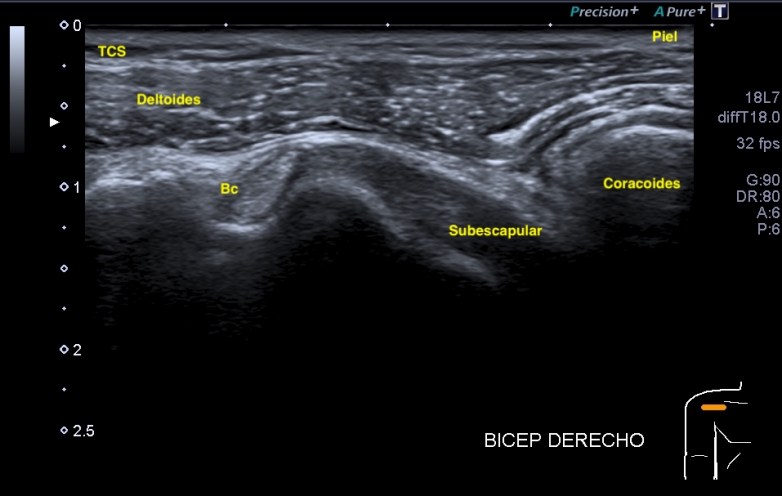

1. Tendón del Bíceps eje corto. La relación anatómica del Bíceps en la corredera bicipital con el Téndón del Subescapular y musculatura adyacente. Eje corto.

👉🏻Bíceps hiperecogénico.

👉🏻Subescapular no tensionado. Anisotrópico.

👉🏻Coracoides medial a todo.